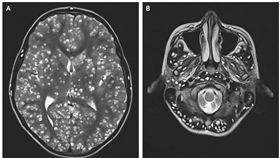

18歲男癲癇送醫 腦內住滿寄生蟲

少年癲癇發作送醫,結果掃描檢查過後竟然發現大腦裡面遍...